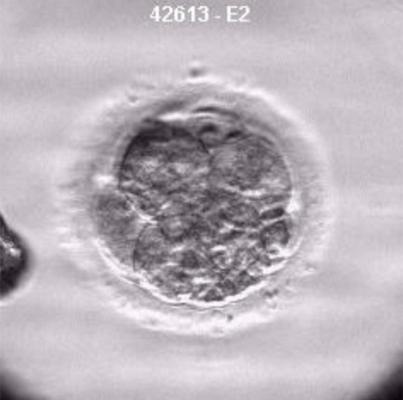

El objetivo del estudio realizado en Clínica Tambre era comprobar la implicación del estrés oxidativo en la baja respuesta ovárica en pacientes sometidas a tratamientos de Fecundación In Vitro (FIV), cuya prevalencia oscila entre el 9 y el 24% de los casos. Los resultados han permitido comprobar concentraciones de marcadores de estrés oxidativo y sustancias antioxidantes en el líquido folicular de pacientes con baja respuesta a la estimulación ovárica frente a donantes de ovocitos fértiles, y pacientes con alta respuesta. Estos resultados, “abren la puerta hacia la unificación de las terapias antioxidantes para aquellas mujeres con peor pronóstico sometidas a un tratamiento de FIV. De hecho, ya existe la tendencia de indicar una dieta antioxidante con suplementos en pacientes infértiles”, explica la doctora Núñez.